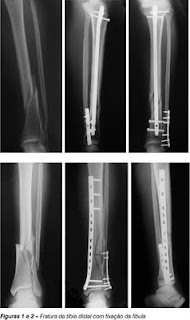

Reabilitação de Fracturas da Tíbia e Peróneo

Imagem 2: Classificação de fracturasFormas clínicas de Fracturas da Tíbia:

Fracturas associadas da tíbia e peróneo – forma mais frequentes

Fractura isolada da diáfise tibial – forma menos frequente

Fractura bilateral – associada a traumatismos violentos (inferior a 5%)

Fracturas associadas da extremidade afectada (luxações tíbio-peroneais superiores;

fracturas da tibiotársica; lesões ligamentares do joelho; fracturas do fémur);

Traumatismo de alta energia gerado por impacto directo que pode provocar fracturas transversas ou cominutivas, que frequentemente são expostas.

Traumatismo indirecto e de baixo impacto resultante da entorse do pé fixo no chão ou de queda de baixa altura que pode provocar um padrão de fractura espiral ou oblíquio.